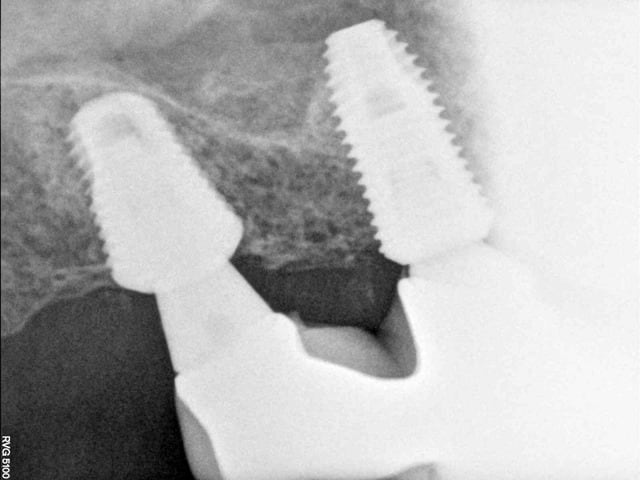

comme ce petit cas

la 2ème radio est prise 18 mois après la 1ère

PS pour Gulguch c'est bien un implant de 6 mm de diamètre en distal et pourtant pas la moindre perte osseuse...

si tu regarde bien la radio il y a une "esquille" (tarte ou /et ciment) entre les deux piliers et mauvais "joint" donc il ne faut peut être pas accuser l'implant dans ce cas là.

je voulais justement signifier l'inverse cad malgré des "soucis" de tartre et joint le niveau osseux est au dessus de l'implant